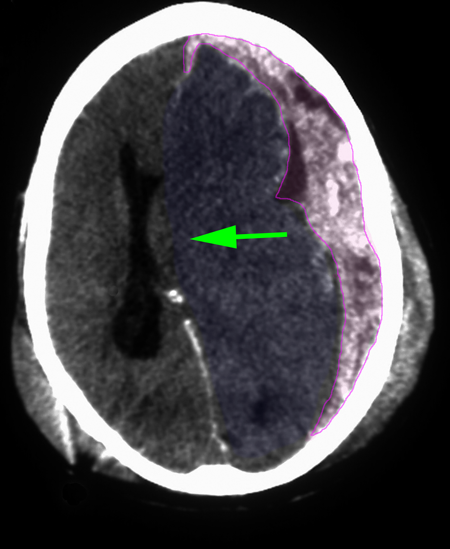

Υποσκληρίδιο αιμάτωμα εγκεφάλου αριστερά. |